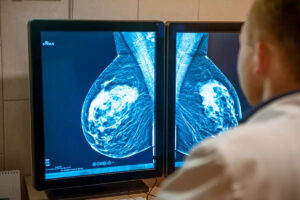

A mamografia é um exame de diagnóstico por imagem que utiliza raios-X para avaliar o tecido mamário. Esse procedimento desempenha um papel essencial na detecção precoce do câncer de mama, aumentando consideravelmente as chances de um tratamento bem-sucedido.

Quando realizado regularmente, o exame permite identificar alterações mínimas, muitas vezes imperceptíveis ao toque, como microcalcificações e pequenos nódulos. Esse diagnóstico precoce possibilita intervenções menos invasivas e melhora a qualidade de vida das pacientes.

A mamografia digital se diferencia da convencional pela captação das imagens, que são processadas e armazenadas eletronicamente. Isso permite ajustes no brilho e contraste, tornando a análise mais detalhada e precisa.

Outra vantagem da mamografia digital é a possibilidade de ampliar regiões específicas da imagem sem perda de qualidade. Isso facilita a detecção de alterações mínimas e reduz a necessidade de repetir o exame. Caso seja necessária uma investigação mais aprofundada, o médico pode acessar as imagens de maneira rápida e compará-las a exames anteriores.